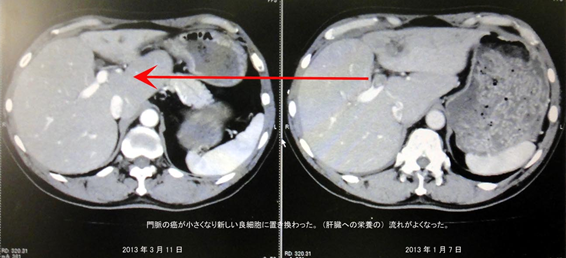

『なんと肝臓の門脈の癌が小さくなるなんて信じられないことが起こったと!!!

リンパのガンもわかないぐらい小さくなった』

ガンが小さくなって正常な細胞に変化してきているようです。